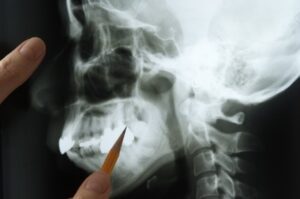

What are All-on-4 implants? All-on-4 implants are a dental solution for replacing an entire arch of teeth using just four strategically placed implants. This method provides a stable, lasting foundation for prosthetic teeth.